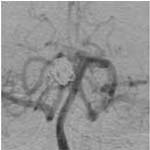

³úµ¿¸Æ·ù¿¡

ÀÇÇÑ ÁöÁÖ¸·ÇÏÃâÇ÷ÀÇ CT¼Ò°ß ¹× Ç÷°üÁ¶¿µ¼ú¿¡¼

Àü±³Å뵿¸Æ¿¡ µ¿¸Æ·ù°¡ º¸À̰í ÀÖ´Ù.

<¼ö¼ú

Àå¸é> <¼ö¼ú

ÈÄ>

¼ö¼ú

ÈÄ µ¿¸Æ·ù°¡ º¸ÀÌÁö ¾ÊÀ¸¸ç µ¿¸Æ·ù °æºÎ¿¡

Ŭ¸³ÀÌ µé¾î°¡ ÀÖ´Â °ÍÀÌ º¸À̰í

ÀÖ´Ù.